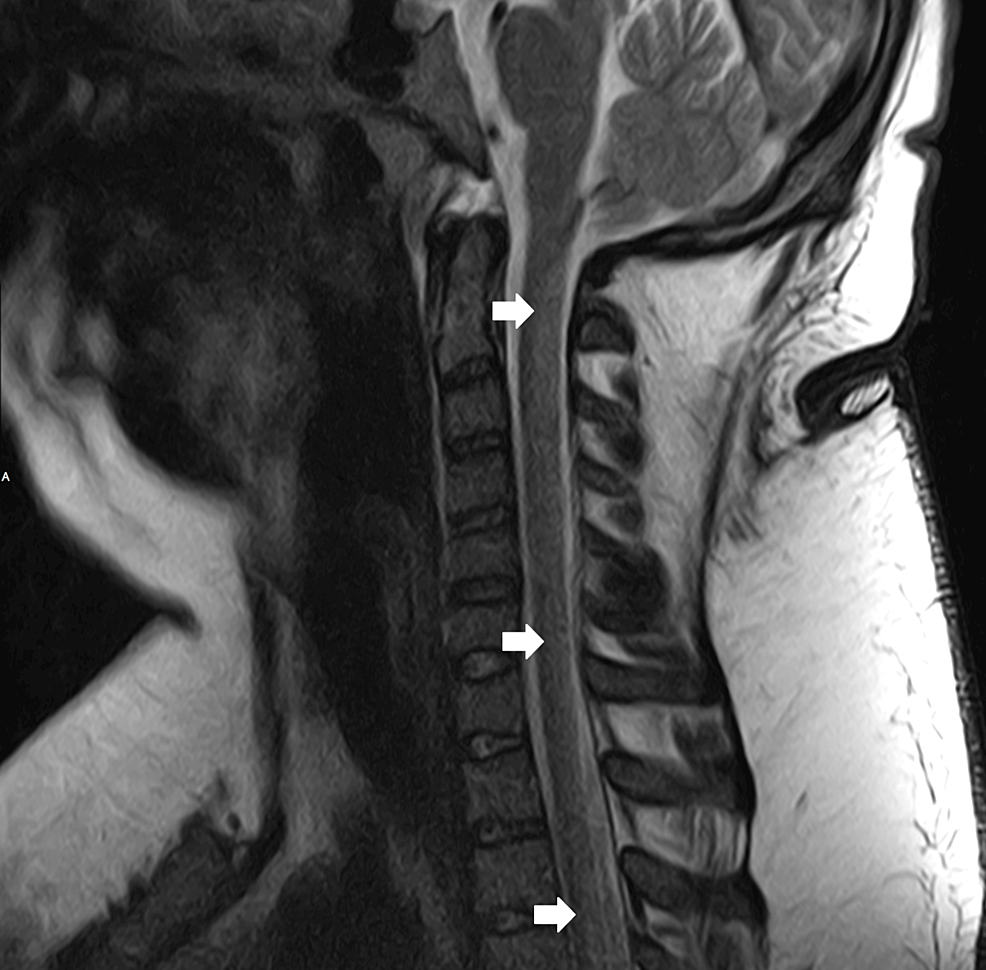

Figure 2 from Pulmonary embolism and deep vein thrombosis caused by Nitrous Oxide Veins Laboratory tests demonstrated normal vitamin b12 (292 pmol/l) and moderately elevated homocysteine (22 μmol/l). In this case, chronic nitrous oxide abuse might be a direct or an indirect factor. The aim of this study. Despite being a known risk factor for cardiovascular disease, the exact pathophysiological mechanism remains. Background —although nitric oxide (no) is known to play an important part. Nitrous Oxide Veins.

(PDF) Isolated cortical vein thrombosis after nitrous oxide use in a Nitrous Oxide Veins Despite being a known risk factor for cardiovascular disease, the exact pathophysiological mechanism remains. Nitrous oxide (n 2 o) has been thought to be a harmless recreational substance by public perception, but it has been linked to. The aim of this study. Ct scan showed thrombosis of the superior mesenteric vein,. Background —although nitric oxide (no) is known to play. Nitrous Oxide Veins.